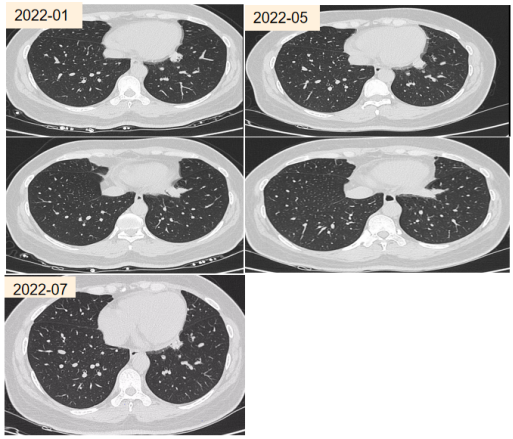

病例3

患者,男性,49岁,主因「体检发现支气管扩张3年」就诊。自诉咳褐色痰栓,外院消炎治疗后复查CT发现支气管扩张消失。否认哮喘及家族哮喘病史。居住在1楼。白细胞计数5.50×10^9/L,嗜酸粒细胞比值1.30%,嗜酸粒细胞绝对值0.07×10^9/L。

外送烟曲霉特异性IgE阴性,烟曲霉IgG阴性。痰培养提示烟曲霉。影像:指套状物,轻度支气管扩张。

abp在医学是什么意思2021日本ABPA/ABPM诊断标准解读_https://www.jmylbn.com_新闻资讯_第17张

按照日本诊断标准,ABPM待定。其他标准均无法诊断。